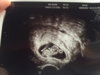

Takk!Gratulerer med dagen som var!

Jeg har fått time til OUL 1.des![]()